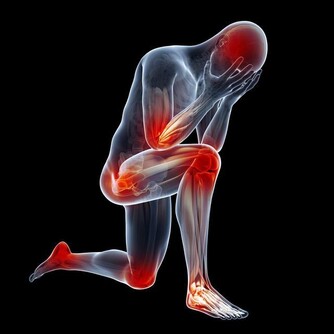

專家表示,千萬不要小看濕疹,若不規範治療,將急癢難耐,逼得患者抓的遍體鱗傷,滲液、乾燥、流血、結痂、粗糙肥厚與裂口,瘙癢變成鑽心的癢,夜裡難以入睡影響日常的生活。而濕疹出現的最常見部位一般在四肢及腰部,尤其以下肢最為明顯。

好發的部位是皮膚油脂分泌最少的小腿前側以及腰部附近。